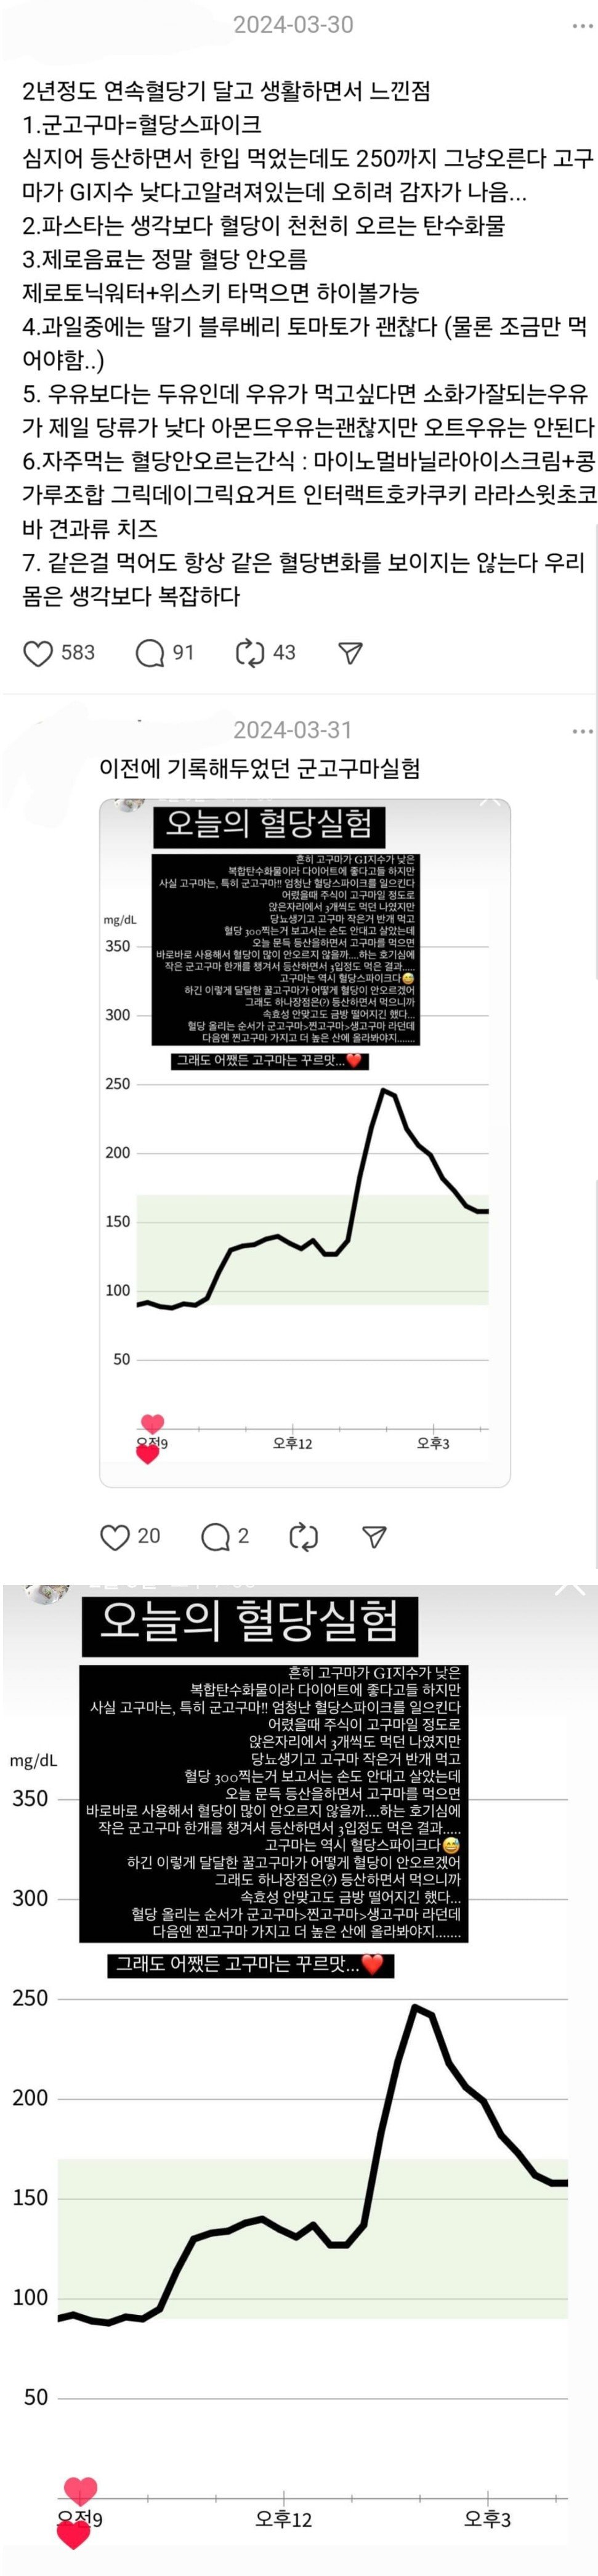

당뇨인이 직접 해 본 고구마 실험